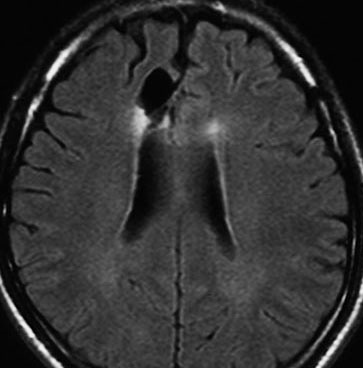

2000年頃の例です。てんかんで発症した20代の女性です。左前頭葉のグリオーマで,手術でほとんどで摘出 subtotal removalして,深部白質に残った病変を経過観察しました。MRIは術後のものです。Ip, 19qはFISHで欠失なし。MIB1は1-2%と低く,MGMTメチレーションなし,diffuse astrocytoma WHO grade 2と組織診断されました。大学病院でしたが当時はIDH遺伝子診断はしておらず,びまん性星細腫グレード2でした。これもまた当時の標準的な考えで,進行があるまでは経過観察としました。

2年後に急激な進行 rapid progressionしました。ガドリニウム増強所見も出現しました。IMRTで59.4Gy/27分割の放射線治療とテモゾロマイド化学療法をしましたが,腫瘍は抑制できませんでした。

放射線治療後も進行して,白質に沿った浸潤伸展をしました。脳幹部橋の右側まで浸潤 invasionしています。この伸展は星細胞系腫瘍の特徴でもあります。

2016年分類では,diffuse astrocytoma WHO grade 2です。しかしこれはおそらく,2021年分類では IDH wild-type astrocytoma grade 4とされます。